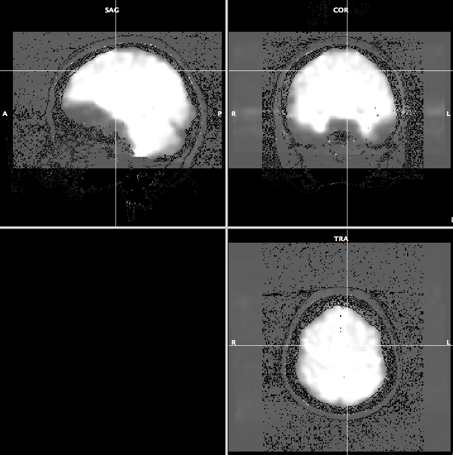

In this process, we will make the low resolution anatomical image to have the same view as the high resolution anatomical image for later alignment.

- Open anat.low.vmr file.

- Select "Spatial Transf" and click "To Sag" if the SAG view of the anat.low.vmr dataset does not show sagittal plane.

- Click "Iso-Voxel" and you will see "Iso-Voxel Transformation" dialogue. Check the Source voxel size is correct and press "OK".

-> You will get anat.low_SAG_ISO.vmr file.